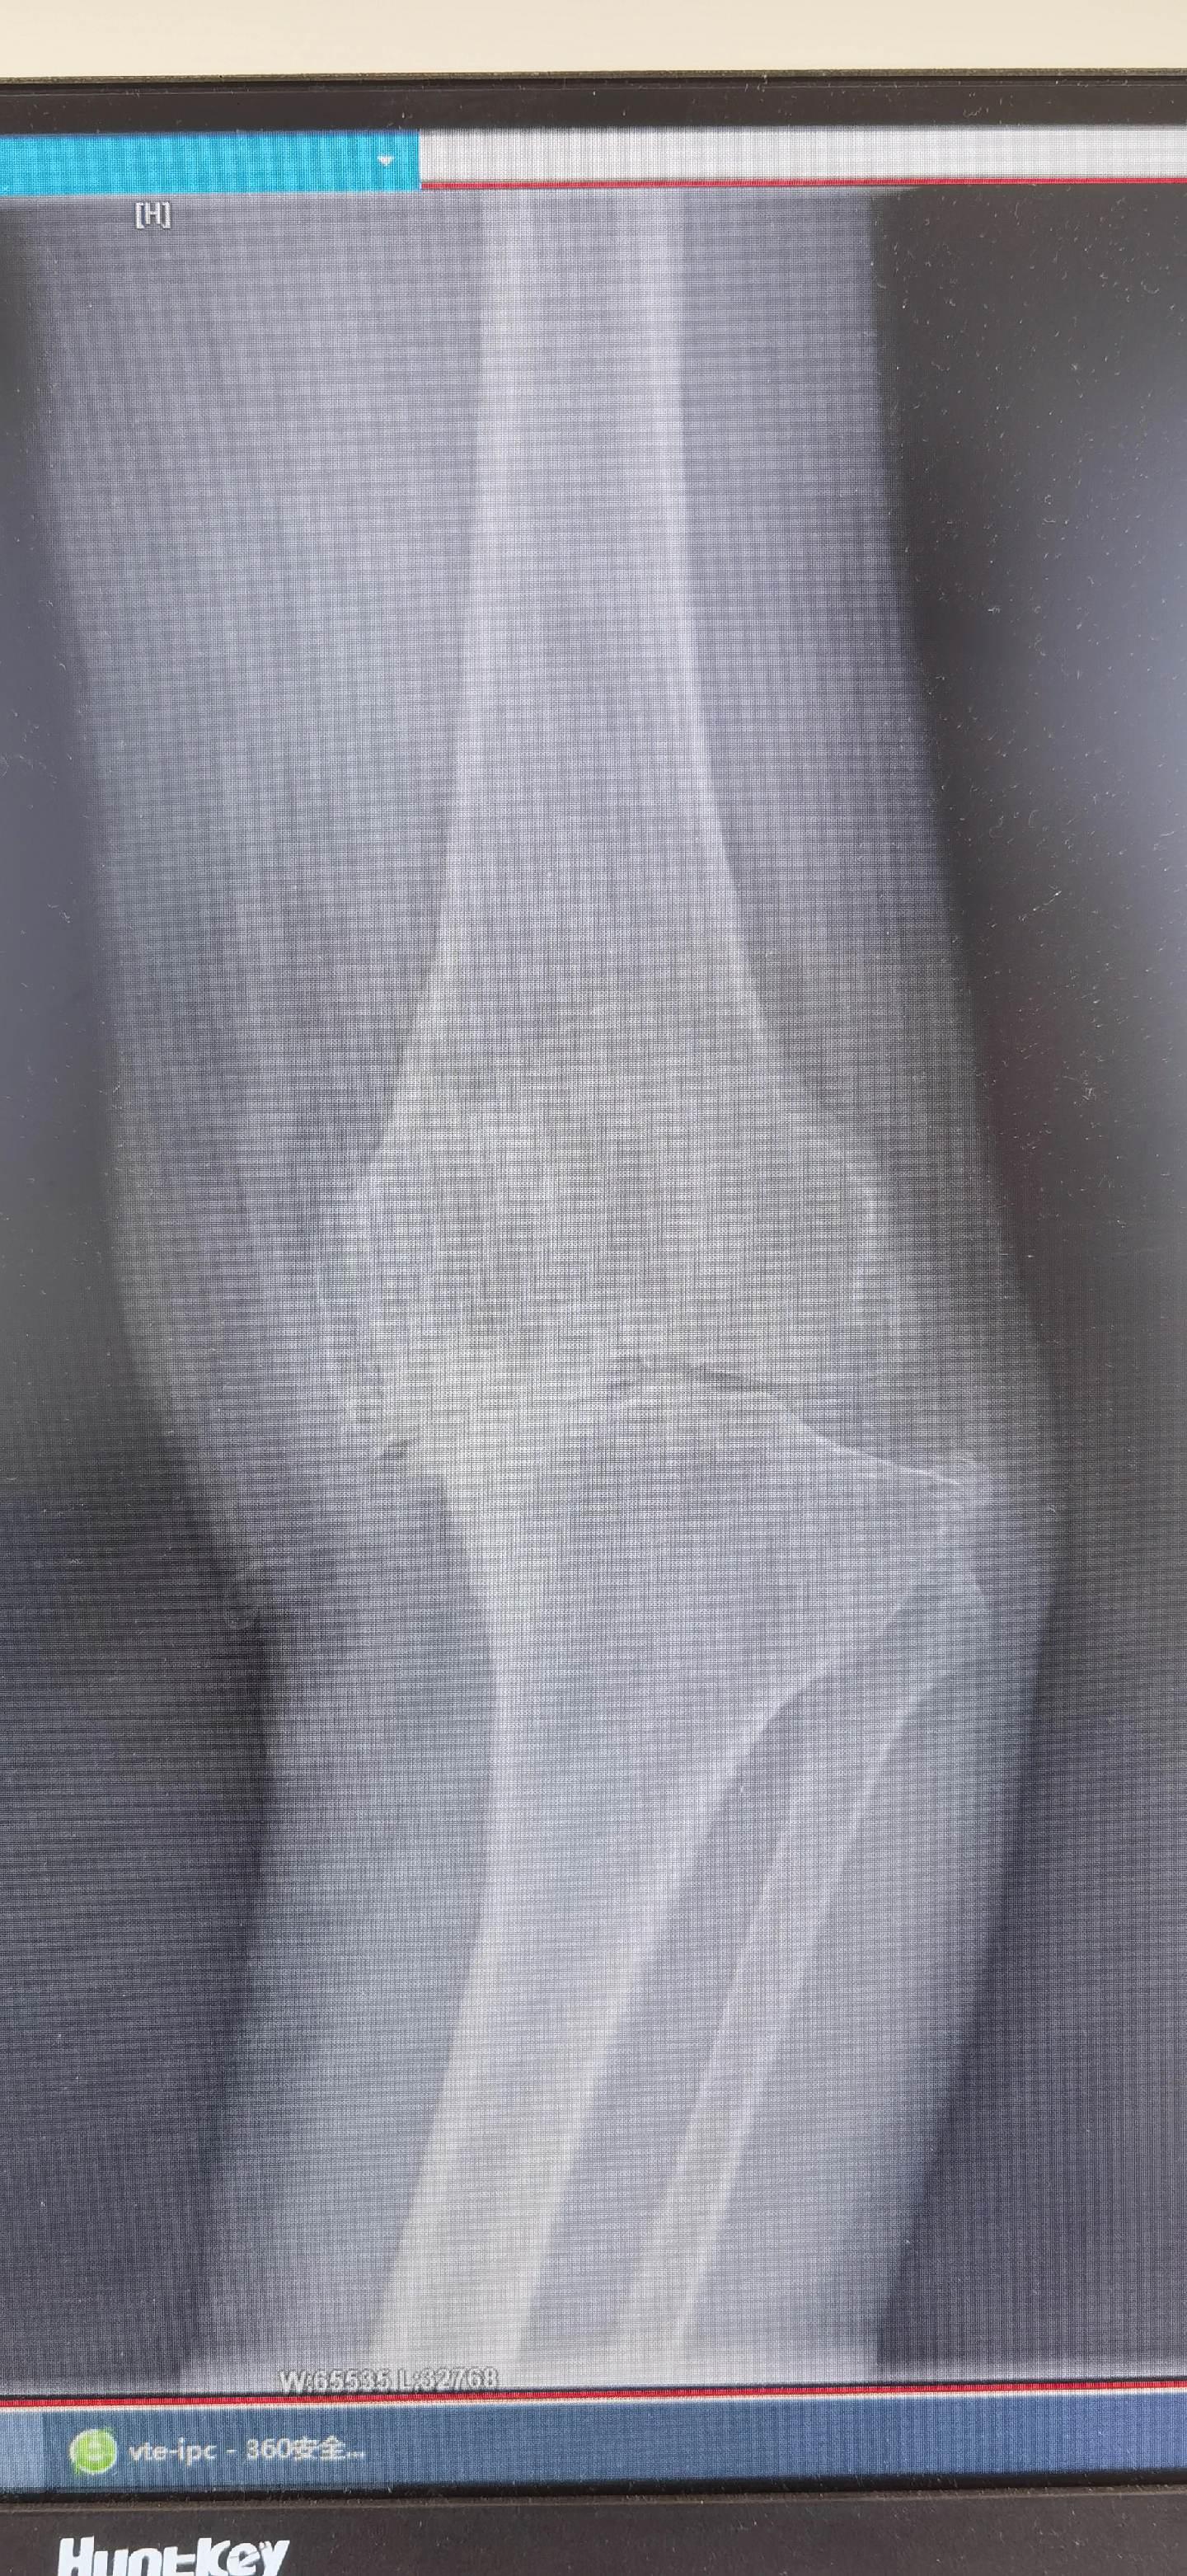

膝关节置换TKA.骨关节炎重度内翻合并屈曲挛缩畸形,无法行走,一期行双侧TKA,愿每一位患者都能得到有效的治疗,都能早日恢复正常生活🌹